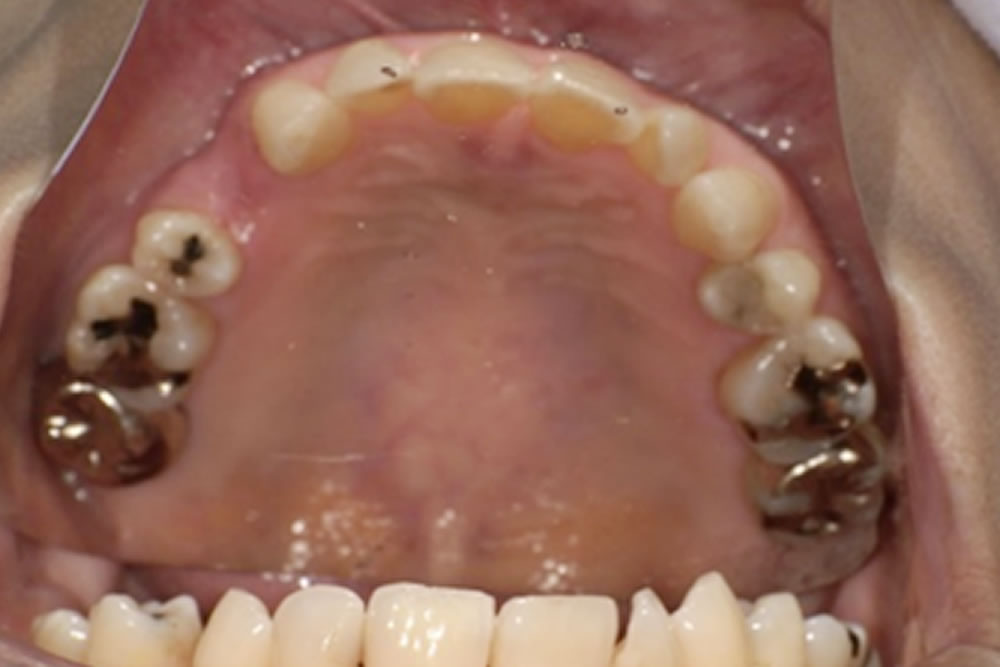

これらの点を踏まえ、最終的に選ばれたのがミラクルデンチャーでした。外科的処置を伴わず、歯を削ることもなく欠損部を補えること、そして審美性が高いこと、清掃がしやすいことなどが主な理由です。ミラクルデンチャーは特殊な「キーとロック」に似た構造によって高い維持力を発揮するため、最初は取り外しに少しコツが必要ですが、慣れると外れにくく快適に使用できるという特徴があります。

義歯の設計では、口腔内の形態に合わせて、床の前方を小さく・後方を大きめにするなど細かな工夫を行い、装着時の違和感が少しでも軽減されるよう調整しました。

製作したミラクルデンチャー